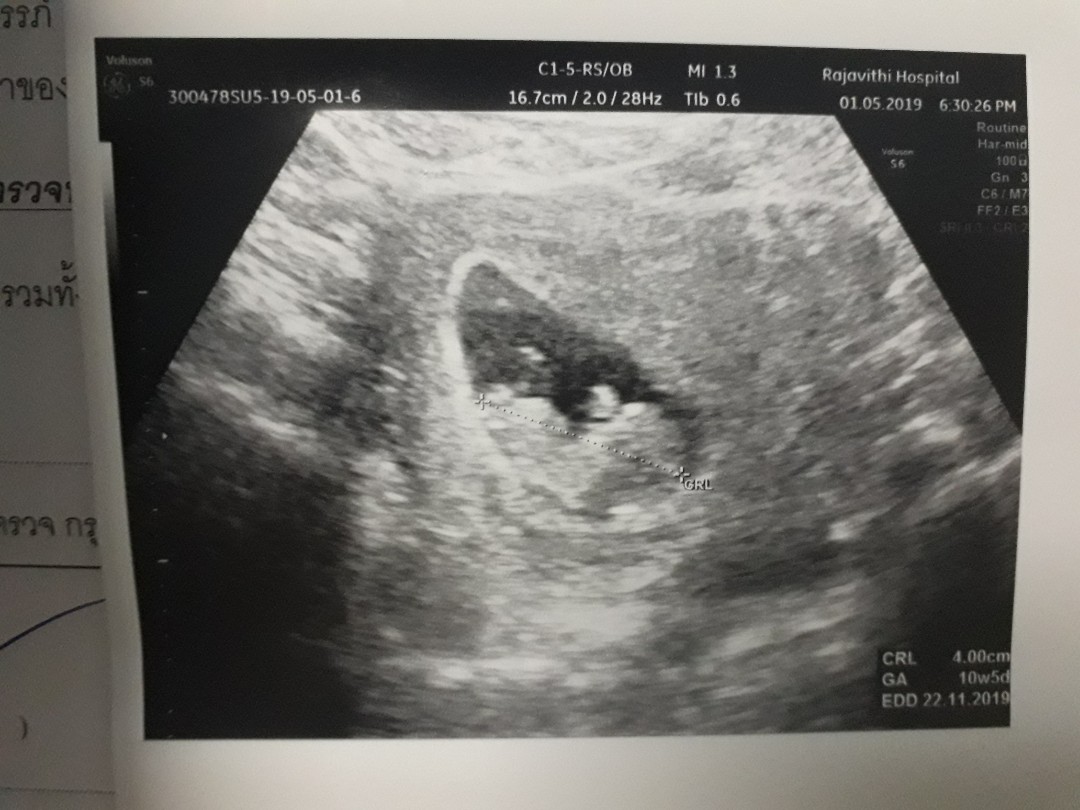

ตอนซาวด์ 10w 5d ค่ะ ตอนนี้ 17w 4d ล๊าววว

ตอนซาวด์10w5d ตอนนี้ 17w4d ตื่นเต้นทุกครั้ง